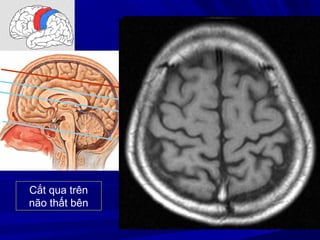

Cắt qua trên

não thất bên